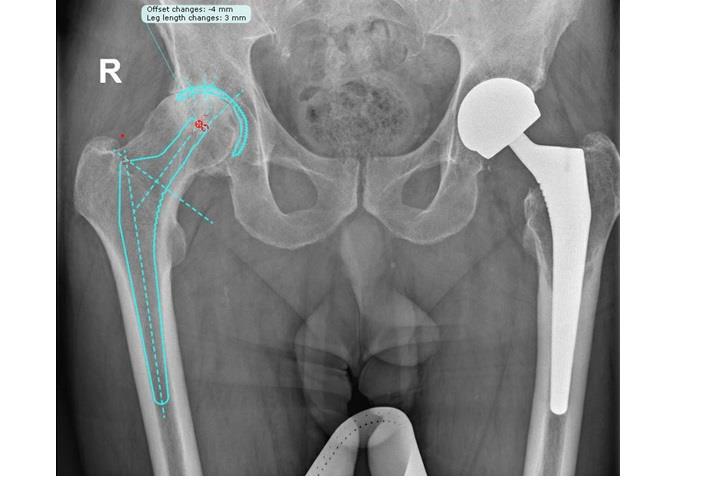

ישנם סוגים שונים של משתלים המשמשים להחלפת מפרק הירך. הבחירה במשתל המיטבי תלויה במאפיינים השונים של המנותח, הן מבחינת רמת תפקודו ומצבו הרפואי והן מבחינת מבנה ואיכות העצם. על מנת לקבל את התוצאות הטובות ביותר יש לבצע תכנון ממוחשב של הניתוח כדי לתכנן את זוויות החיתוך ולבחור את המשתל המותאם לאנטומיה של המנותח.

טכניקת קיבוע המשתלים לעצמות חשובה גם היא לצורך הבטחת השרידות של המשתל ומניעת סיבוכים. בחירה במשתל המתאים לאנטומיה של החולה תאפשר גם אחיזה טובה וממושכת בין העצם לבין השתל. כאמור, קיימים משתלים בגדלים ועיצובים שונים והבחירה במשתל המתאים ביותר תתבצע על פי תכנון ממוחשב. אם קיימת עצם חדשה ומדולדלת (כמו למשל במטופלים עם אוסטיאופורוזיס), הרופא המטפל ישקול להדביק את המשתלים בעזרת מלט עצם (צמנט) – חומר המשמש בניתוחי החלפת ברכיים וכן גם בתחום רפואת השיניים. אם עצמות המטופל חזקות, לרוב ייבחר משתל הנצמד בחוזקה אל העצם ללא צמנט.